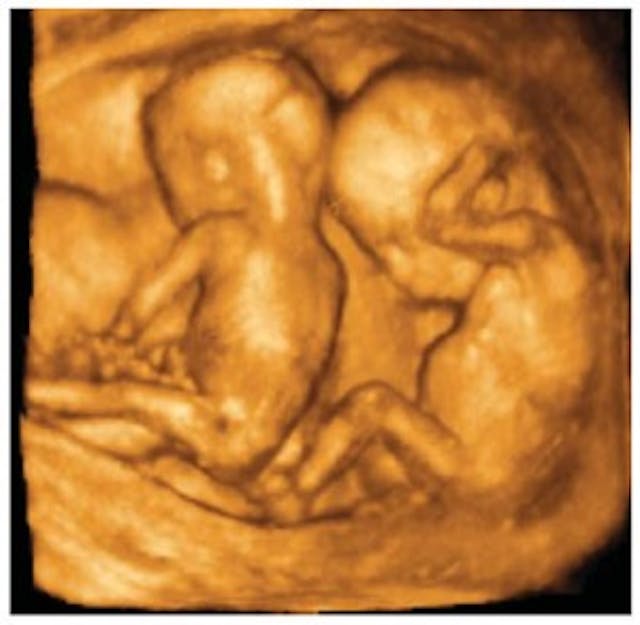

The procedure is gruesome, as anyone who has seen it, including Rashbaum, will attest. One of his former interns remembers watching Rashbaum do a D&E on well-developed twins one hot summer day. He intently leaned in closely and methodically pulled piece after piece of the fetuses out of the mother’s uterus, ignoring the attending staff’s whispers of horror — “It’s twins. It’s twins” — to each other. The intern reacted violently, running home, throwing up, and asking herself, “Is this right?